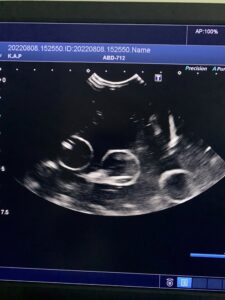

下の写真に写っているエコー検査画像は、水の中に浮かんだ「あるもの」を2つの断面で見たものです。さて、「あるもの」とはなんでしょう?

※臓器ではありません。身近にある日用品(?)です。